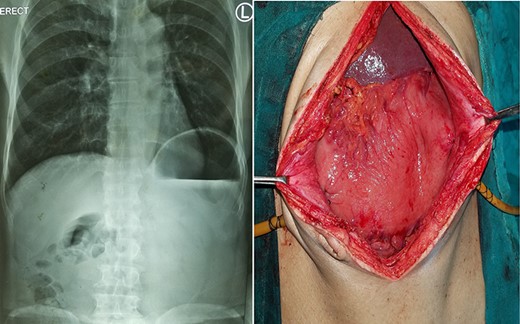

Chest X-ray and CT showing an elevated left hemi-diaphragm with a large sub-diaphragmatic air-fluid level.

Intraoperative laparoscopic view of left diaphragmatic eventration.

A 19-year-old male with no known co-morbidities presented to the emergency department with 2-day history of severe upper abdominal pain and vomiting. He complained of similar episodes over the past 2 years, which used to get relieved spontaneously. On examination, the patient was tachycardic (110 bpm) with normal blood pressure and normothermic. The upper abdomen was asymmetrically distended, non-tender with a tympanic note. The laboratory investigations were within normal limits. Chest X-ray revealed markedly elevated (>4 cm) left hemi-diaphragm, huge gastric shadow with an air-fluid level and shift of mediastinum toward the right side (Fig. 1). Acute gastric volvulus was suspected based on the above finding, which was confirmed with contrast CT. Patient underwent initial laparoscopic evaluation, which was converted to open procedure. Intraoperatively, there was an organo-axial volvulus without any vascular compromise secondary to diaphragmatic eventration. It was de-rotated, decompressed and anterior abdominal wall suture gastropexy done. The freely mobile stomach was further reinforced with sham (trans-seromuscular) gastrojejunostomy. Left diaphragmatic eventration was plicated with polypropylene suture number 1 (Fig. 2) for which it required open conversion. Postoperative period was uneventful and discharged on Day 6. At 16-month follow-up, patient is doing absolutely fine.